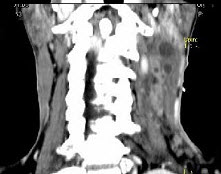

男,67岁,口咽部异物感约8个月,伴口咽部疼痛,患者无明显发热。如图所示最可能的诊断为()。

A、扁桃体结核伴淋巴结转移

B、扁桃体脓肿伴淋巴结转移

C、扁桃体癌伴淋巴结转移

D、扁桃体淋巴瘤

E、下咽癌伴淋巴结转移

C